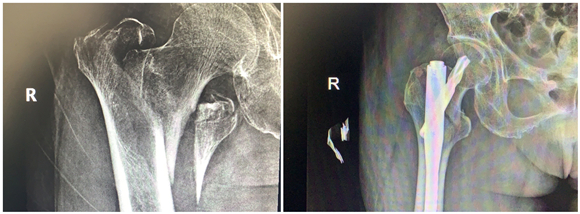

年前,蔡奶奶在家摔了一跤,右側(cè)股骨劇烈疼痛,不能走路,無(wú)法動(dòng)彈。檢查發(fā)現(xiàn)老人右側(cè)股骨粗隆間骨折,當(dāng)時(shí)老人拒絕治療,回家臥床后每況愈下。家人不忍心看著老人這么痛苦,了解到該院骨科擅長(zhǎng)老年性骨折治療,于是帶著老人來(lái)到該院鼓山路院區(qū)骨科就診。來(lái)院后,患者診斷為右股骨粗隆間粉碎骨折,并伴有右下肢深靜脈血栓、褥瘡、肺部感染等并發(fā)癥,情況非常危險(xiǎn),此類骨折又稱為“死亡骨折”。據(jù)了解,“死亡骨折”是指老年人的髖部骨折,常常是股骨粗隆間骨折和股骨頸骨折,其中骨折后臥床引起的并發(fā)癥會(huì)導(dǎo)致死亡,死亡率高達(dá)40%,又稱人生最后一次骨折。

此類手術(shù)風(fēng)險(xiǎn)大,醫(yī)生在告知患者家屬手術(shù)風(fēng)險(xiǎn)、術(shù)后康復(fù)、搶救方案等情況后,家屬打消了顧慮,決定盡快給老人家安排手術(shù),擺脫病痛折磨。同時(shí),麻醉科為老人制定了個(gè)性化的麻醉方案。王斌手術(shù)團(tuán)隊(duì)給患者制定了微創(chuàng)手術(shù)方案,通過(guò)三個(gè)小孔來(lái)進(jìn)行固定,避免了大的手術(shù)切口,整個(gè)手術(shù)過(guò)程僅僅耗時(shí)50分鐘,出血量50ml左右。

患者術(shù)后第二天就下地站立行走,X線顯示骨折對(duì)位好,復(fù)查下肢靜脈B超提示少許肌間靜脈血栓。在??漆t(yī)生的康復(fù)指導(dǎo)下,患者褥瘡、肺部感染也很快消失了。術(shù)后第7天,患者康復(fù)出院。